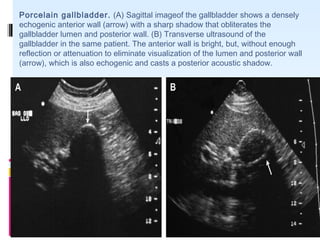

PORCELAIN GB

 A porcelain gallbladder refers to extensive calcium

encrustation of the gallbladder wall.

 The term porcelain gallbladder has been used to

emphasize the blue discoloration and brittle

consistency of the gallbladder wall at surgery

 Association between porcelain gallbladder and

gallbladder adenocarcinoma- 22-30 % .

 Cholecystectomy routinely performed when a

porcelain gallbladder is identified.

Porcelain gallbladder. (A) Sagittal imageof the gallbladder shows a densely

echogenic anterior wall (arrow) with a sharp shadow that obliterates the

gallbladder lumen and posterior wall. (B) Transverse ultrasound of the

gallbladder in the same patient. The anterior wall is bright, but, without enough

reflection or attenuation to eliminate visualization of the lumen and posterior wall

(arrow), which is also echogenic and casts a posterior acoustic shadow.